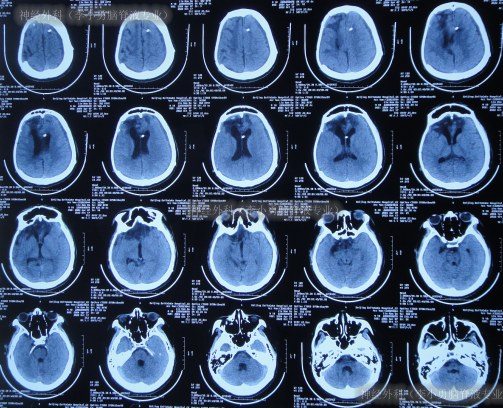

虽又再次出现脑积水但2022年5月5日(脑室腹腔分流术后38天),仍进行了右侧额颞顶部颅骨缺损修补术(图-12)。

图-12:2022年5月6日头颅CT

但颅骨修补术后1周即2022年5月13日(脑室腹腔分流术后45天),患者反而出现意识变差,由清醒变为嗜睡,肢体活动也变差,且肢体肌张力增高,查头颅CT(图-13)后给予保守治疗。

图-13:2022年5月13日头颅CT

该院继续治疗半月,但患者病情进一步加重为昏迷,期间3次查头颅影像(图-14)。

图-14:3次查头颅影像

因昏迷加重于2022年6月2日(颅骨修补术后27天即脑室腹腔分流术后65天),查头颅CT示仍脑积水(图-15);进行了腰椎穿刺示颅压较高。

图-15:2022年6月2日头颅CT

入院时头颅CT示颅骨修补术后,脑分流术后仍脑积水(图-17)。

图-17:2022年6月9日头颅CT

入院后次日即2022年6月10日,拔除了原脑室腹腔分流管+脑室外引流术(图-18)。

图-18:2022年6月10日头颅CT

住院54天即2022年8月2日,头颅CT示脑室进一步缩小(图-25)。

图-25:2022年8月2日头颅CT

住院65天即2022年8月13日,查头颅CT示脑室变小,颅内感染也进一步减轻(图-26)。

图-26:2022年8月13日头颅CT

住院111天即2022年9月28日,病情进一步好转为:意识清楚,言语交流正常,饮食变正常,右侧肢体活动正常,左侧肢体活动差些(图-27);头颅CT示引流术后状态,未见异常(图-28)。

图-27:2022年9月28 日

图-28:2022年9月29日头颅CT

待脑脊液各项化验达标后于2022年10月8日,进行了脑室腹腔分流术(图-29)。

图-29:2022年10月8日头颅CT